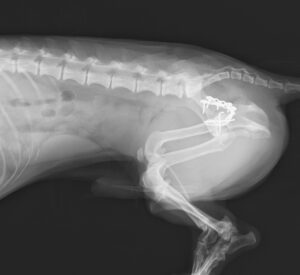

交通事故で当院夜間救急外来へ来院しました。右後肢に重度の疼痛と内出血を認め、X線検査にて複数箇所の「骨盤骨折」が見つかりました。幸い他に大きな致命傷はありませんでしたが、念の為、点滴や痛み止めを使用しながら内科治療を実施し、受傷から3日後に骨盤骨折の整復術を行いました。複雑な場所の骨折だったため、小さいプレートを駆使しながら正しい位置で固定。6週間後には元気に走り回っています。